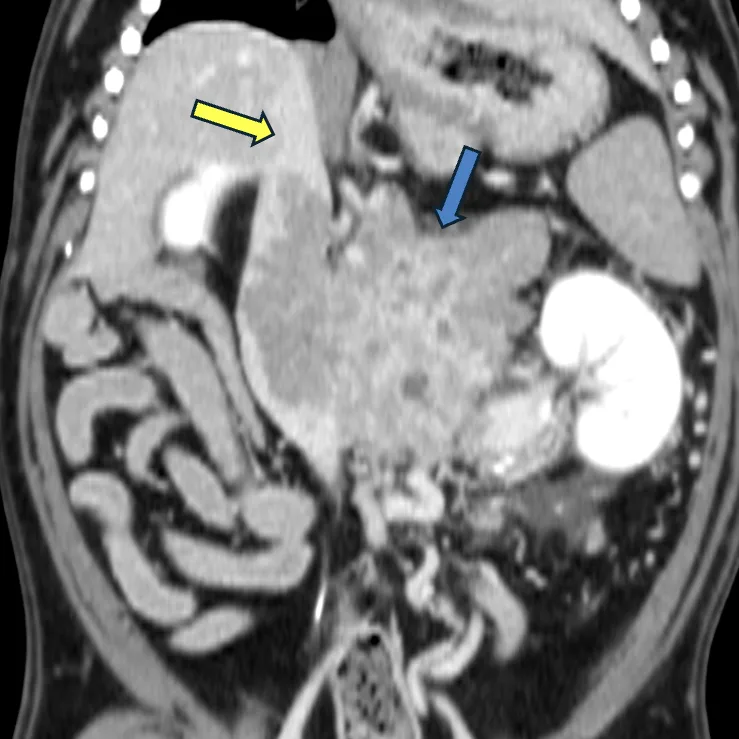

CT検査

・腫瘍のサイズ、血管との関連性を評価します。

・下垂体や腫瘍の転移がないかも同時に評価します。

・外科治療を行う場合には必須の検査となります。

前述した検査を行い、副腎腫瘍を機能性腫瘍、悪性腫瘍、副腎偶発腫に分類します。

悪性所見には、副腎腫瘍サイズが2cm以上、血管内浸潤、転移があります。